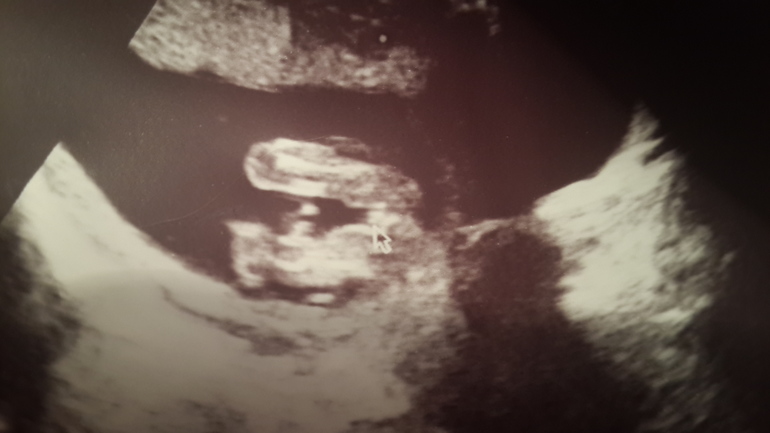

Девчули, кто делал узи на 16-17 неделях и узнал пол - гляньте, если не сложно поделитесь своими фотками. Я просто до сих пор не могу поверить, что наш Марк превратился в девочку!!! Может ошибка, кто помнит фото "бубенчиков"? Девочкины мамы - что скажите??? На фото две согнутые ноги и между ними стрелка указывает на половые органы, подписано "девочка".

У нас на 13 недельке писюн уже торчком был, на 23 - такие основательные коки и писюн. Сомнений совсем никаких не было).

явный пирожочек))))у меня такие же фотки были с дочками))))искать надо )))а вот сейчас в 15 недель сына пообещали,для меня разница очевидна ...они отличаются .Полосочек на моем снимке не видно,а вот яички висят))))